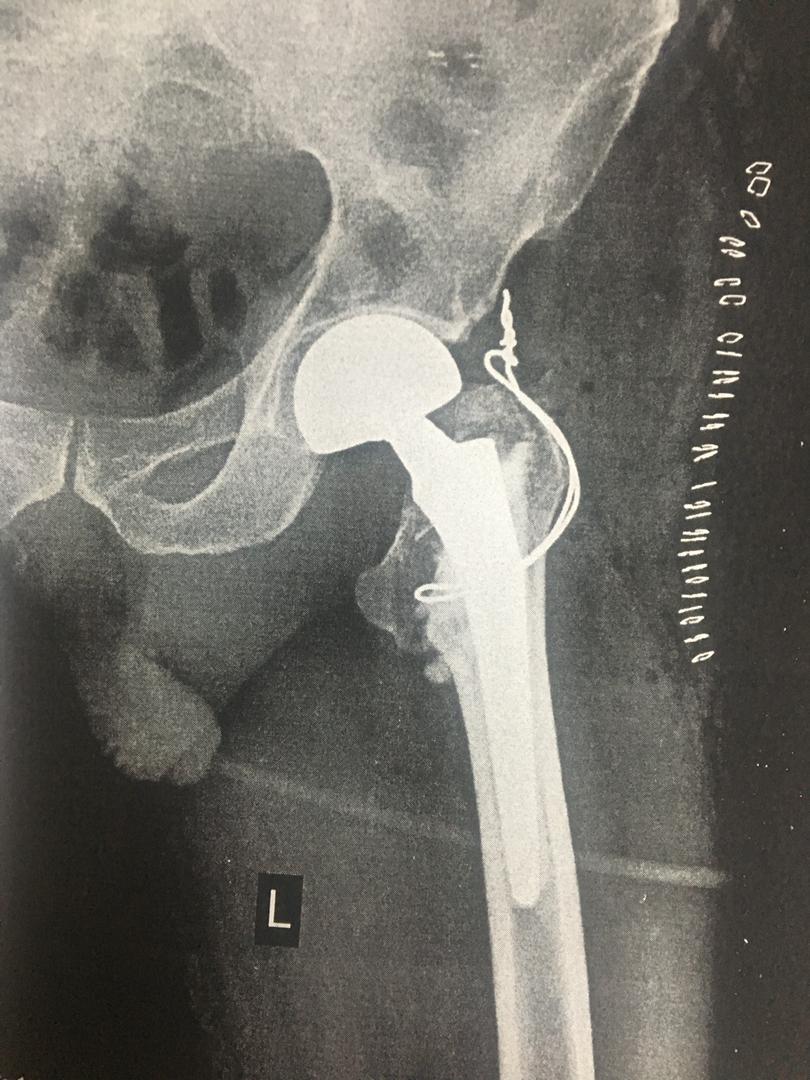

اقای 50 ساله با شکستگی خرد شده ی ران که جراحی و بهبودی کامل

اقای 90 ساله با شکستگی مفصل رانجراحی و بهبودی کامل

اقای 90 ساله با شکستگی مفصل ران که جراحی و راه اندازی شد .